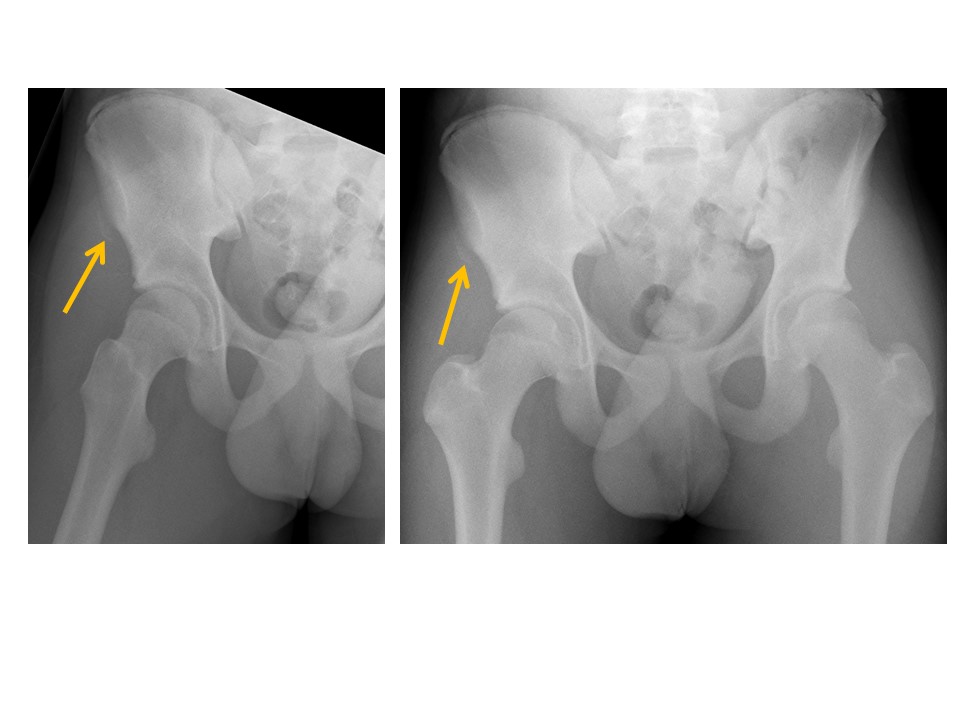

There are fractures of the femoral neck, intertrochanteric region, or subtrochanteric region. [Yes/No]

There are avulsion fractures of the greater or lesser trochanters. [Yes/No]